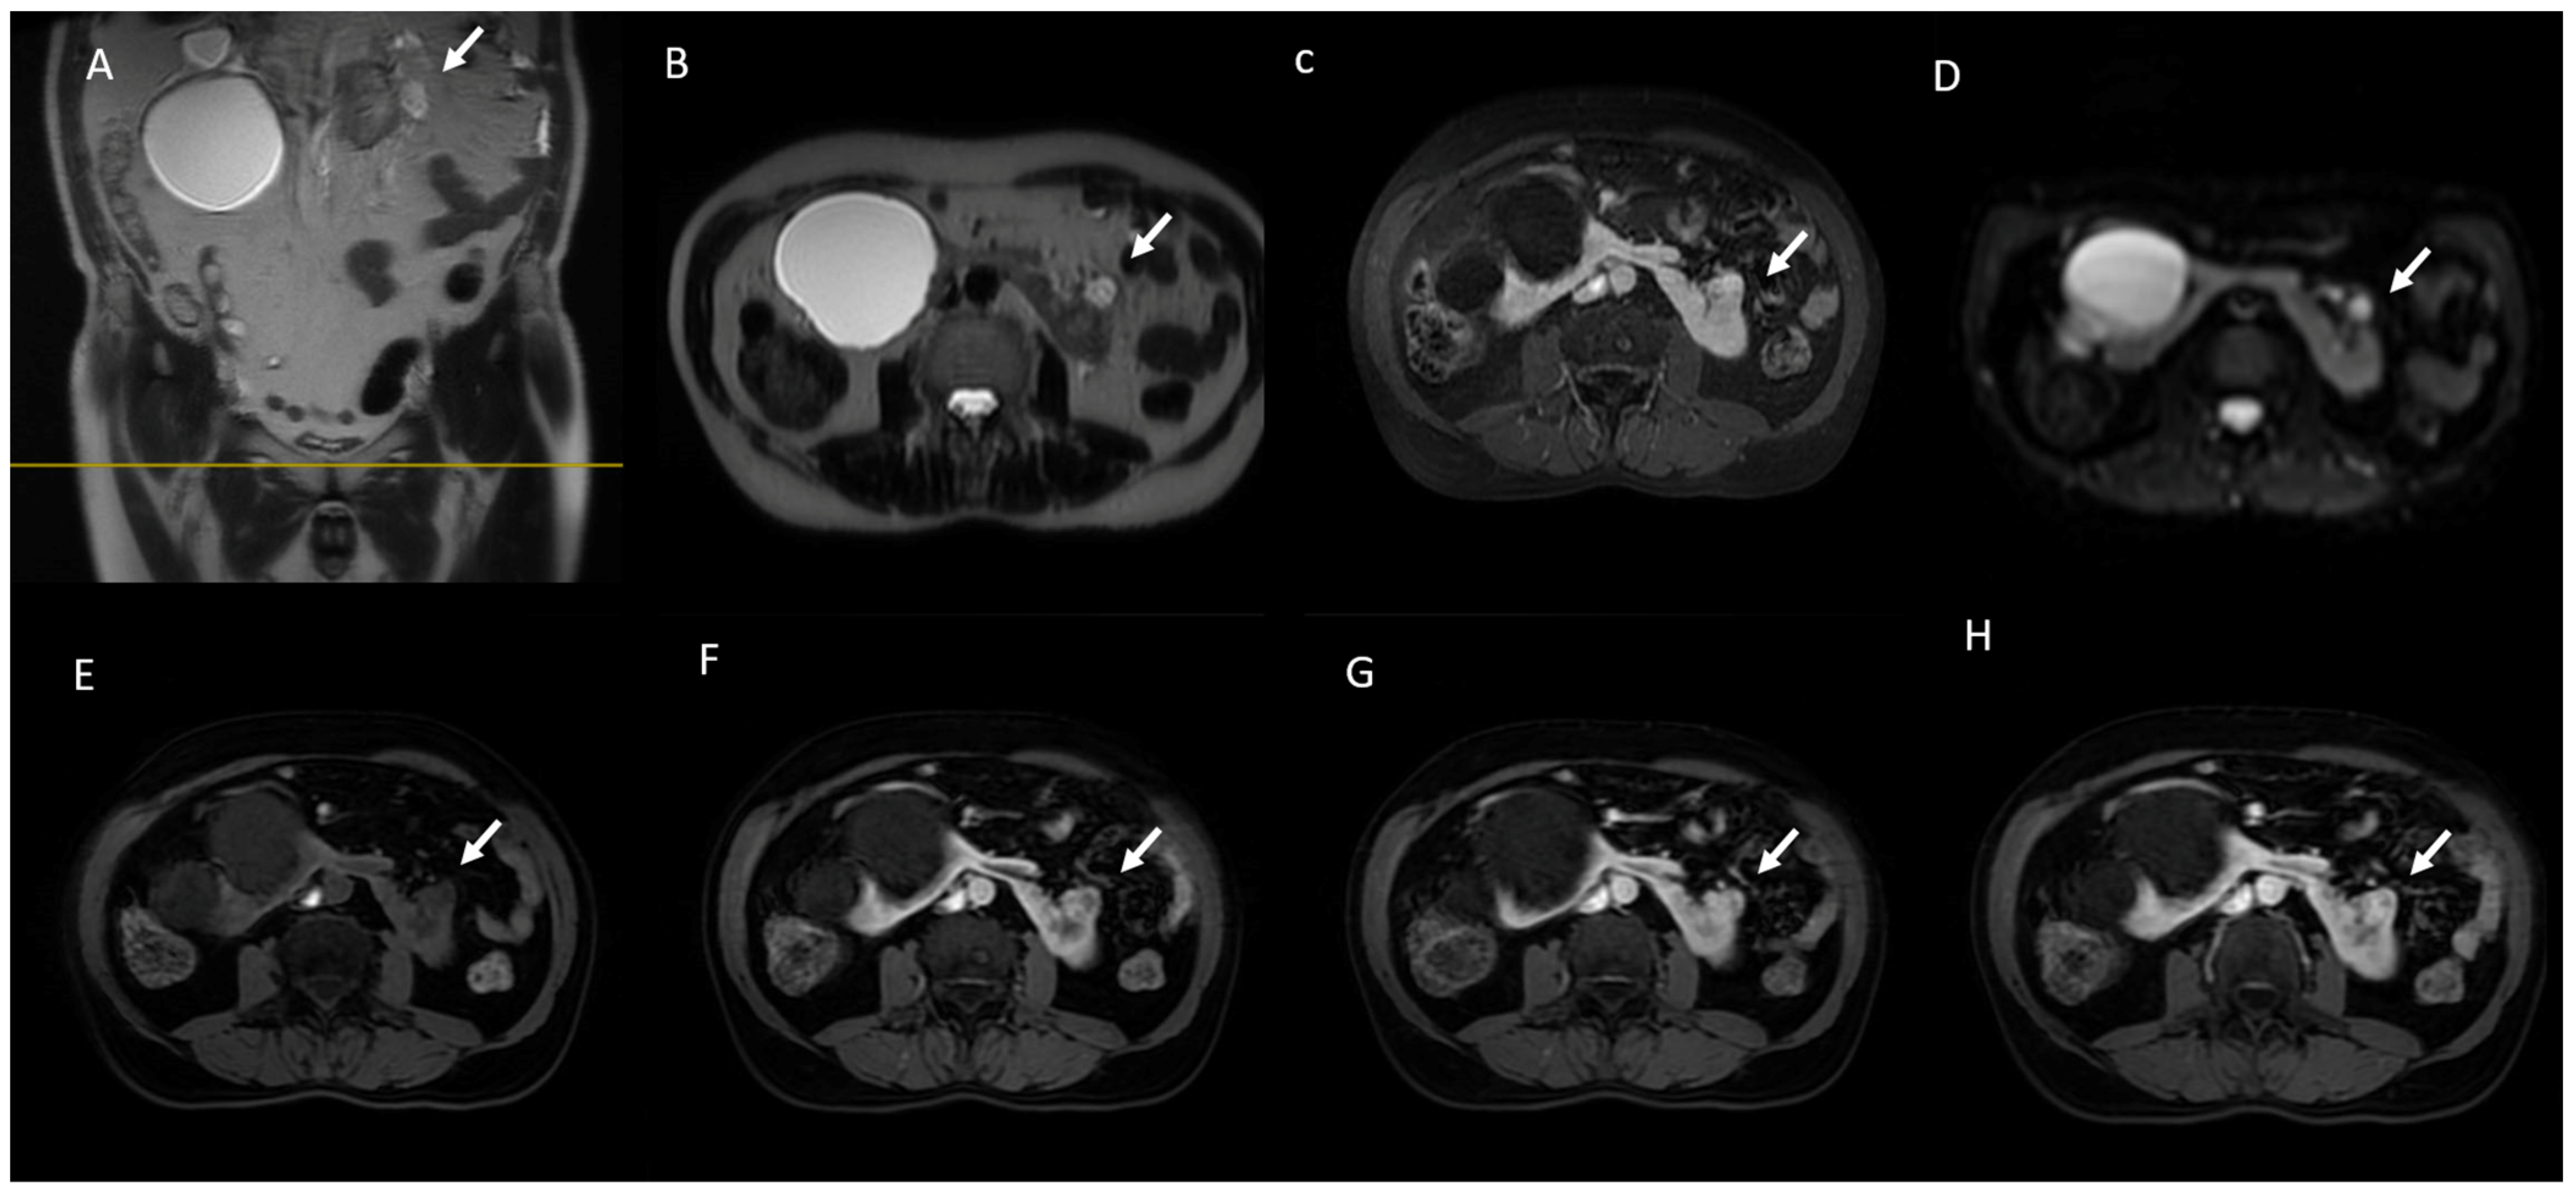

6. MRI Assessment

6.1. T2W Imaging

6.2. CS (IP D OP) Imaging

6.3. Diffusion-Weighted Imaging

6.4. Gadolinium-Enhanced Sequences

6.5. MRI in Bosniak Classification